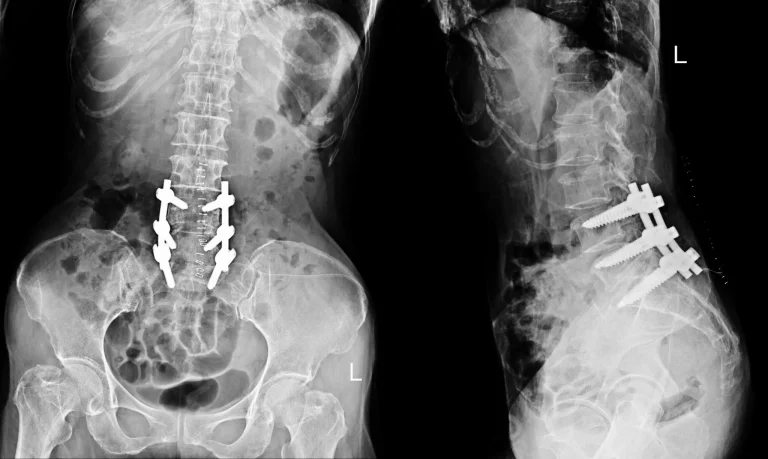

X-ray showing spinal fusion with metal implants in the lumbar region, both front and side views.

Back Pain Gets Worse

X-ray showing spinal fusion with metal screws and rods in the lower back.

Additional Surgery Likely Needed